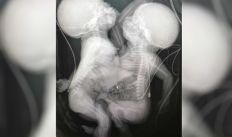

Morrem em SP gêmeas siamesas que estavam ligadas pelo tronco

Bebês nasceram ligados pelo tronco, mas possuíam quatro pulmões, dois corações e duas colunas vertebrais distintas

Gêmeas siamesas separadas respiram com ajuda de aparelhos e seguem em estado gravíssimo

Uma das irmãs possui cardiopatia grave e deve ser operada, mas ainda não há prazo para a realização da operação. Unidas pelo tórax e